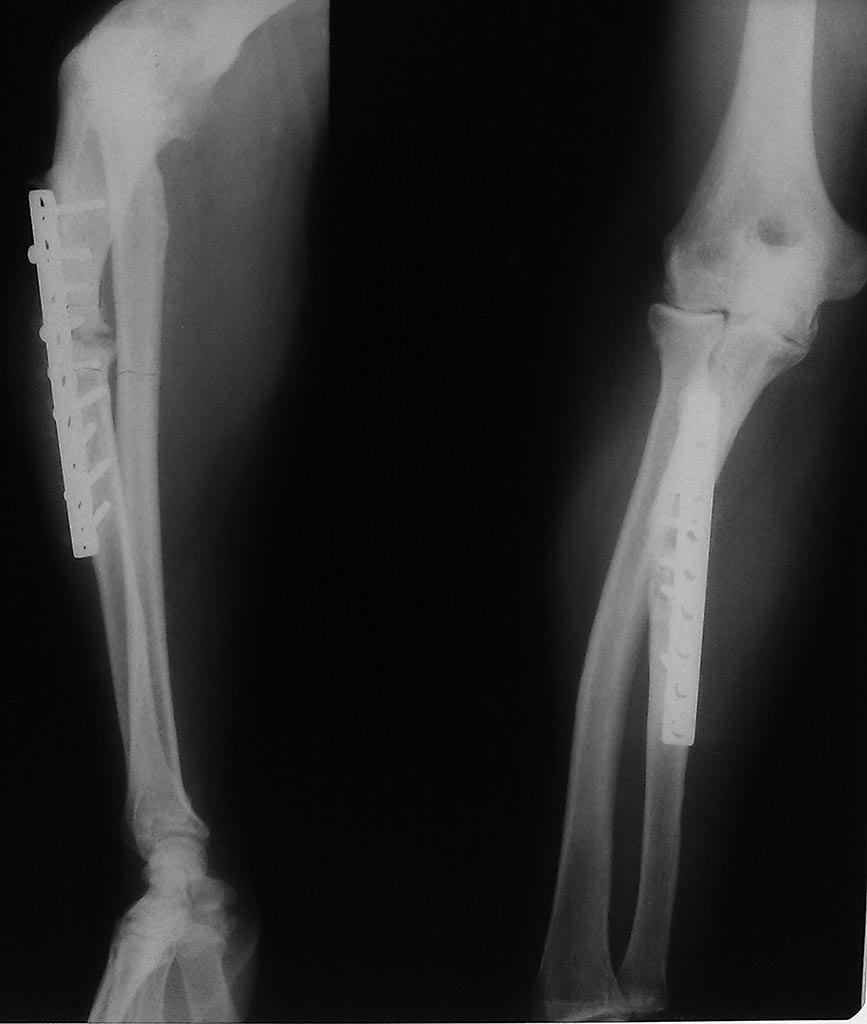

[Ortho] ложный сустав локтевой кости

Прошу прощения за качество снимков, все что прислали на консультацию...